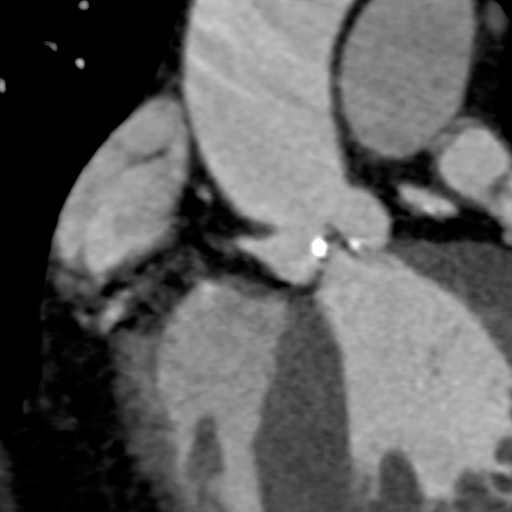

主动脉CT

主动脉瓣环平均直径:22.4mm

左室流出道平均直径:23.2

左冠脉开口:10mm

右冠脉开口高度:14.7mm

患者为功能性二叶瓣,左右瓣叶融合,左冠脉开口低,窦部大,冠脉风险低。

袁义强院长总结了该病例特点:功能性二叶瓣主动脉瓣狭窄,患者有心衰症状,解剖适合TAVR,年龄66岁,存在明确TAVR手术适应症。选择右股动脉入路,根据CT测量分析选择瓣膜大小,窦部情况可,瓣环平均直径22.4mm,选择植入24mm瓣膜。